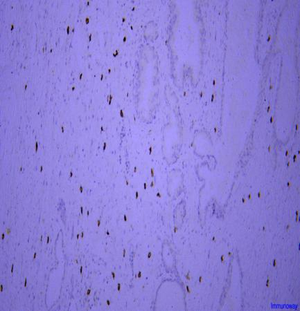

| Immunohistochemistry analysis of paraffin embedded human prostate using c-Kit (GB14021) at dilution of 1: 200 |